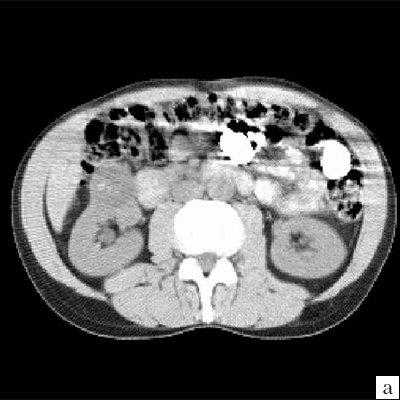

В диагностике мультилокулярных кист ценные сведения можно получить при помощи ультразвукового исследования (УЗИ). По данным разных авторов, достоверность УЗИ в диагностике данной патологии составляет от 94 до 97,3% [1, 8, 9, 11-13]. Эхографически мультилокулярная киста визуализируется в виде многокамерного жидкостного образования округлой формы, расположенного в одном из полюсов почки, с множеством перегородок, как правило, с отложением извести, с четкими ровными контурами и дорсальным усилением эхо-сигнала (рис. 2) [1-3, 6, 8, 9, 12, 14]. Цветное допплеровское картирование (ЦДК) увеличивает чувствительность УЗИ, так как улучшает визуализацию областей с атипичной сосудистой архитектоникой и снижением васкуляризации. При допплерографии отмечаются неспецифические изменения почечного кровотока в виде повышения пульсационного индекса и индекса резистентности, особенно выраженных в сосудах, огибающих образование. Если при УЗИ обнаруживаются утолщение перегородок кист или солидные структуры, в которых при ЦДК регистрируются сосуды, это может быть признаком малигнизации [11, 13, 15-19].

Эхонегативное многокамерное образование неправильной формы, с неровными стенками. Большое количество тонких перегородок в полости образования.

Достоверность комьютерной томографии (КТ) в диагностике мультилокулярной кистозной нефромы, по данным разных авторов, составляет от 95 до 98%. При КТ определяется негомогенное многокамерное образование округлой или неправильно-округлой формы, возможно с капсулой, плотность образования неоднородная, пониженная относительно паренхимы, в полости образования определяется большое количество перегородок (рис. 3). Если при КТ с контрастированием происходит накопление контрастного вещества, это может быть признаком предполагаемой малигнизации [11, 13, 19].

а) До внутривенного контрастирования определяется негомогенное образование неправильной округлой формы с капсулой и едва заметными перегородками, плотность ниже, чем плотность паренхимы почки.

Ультразвуковое исследование. Почки расположены типично, в размерах не изменены, контуры ровные, четкие, подвижность сохранена, полостная система не расширена. Мочеточники не визуализируются. Конкрементов не выявлено. В нижнем полюсе правой почки визуализируется эхонегативное многокамерное образование диаметром до 30 мм, с большим количеством перегородок внутри и единичным кальцинатом.

Заключение: Сложная киста нижнего полюса правой почки (рис. 4).

Округлое кистозное образование с множеством перегородок в полости образования и единичным кальцинатом.

Компьютерная томография. В нижнем полюсе правой почки определяется неоднородное образование, с четкими неровными контурами, округлой формы, в диаметре до 30 мм, неоднородно пониженной плотности от +15 до +18 HU по шкале Хаунсвильда. После внутривенного контрастирования образование не изменят свою форму, размеры и плотность. В полости образования выявляются множественные перегородки, накапливающие контрастное вещество, единичный кальцинат.

Заключение: Сложное кистозное образование нижнего полюса правой почки, больше данных о мультилокулярной кистозной нефроме (рис. 5).

а) До внутривенного контрастирования определяется негомогенное образование округлой формы, с единичным кальцинатом, плотность ниже, чем плотность паренхимы почки.